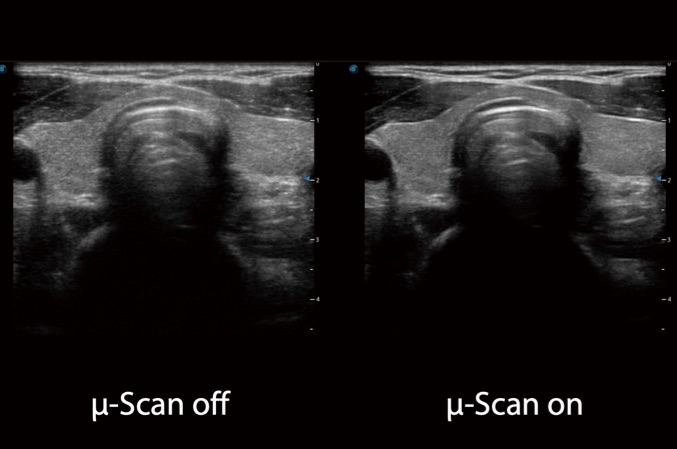

• μ-Scan+新一代微米成像技术

新一代微米成像技术大大提高了器官和病变的可见性。高清对比度分辨率将抑制斑点噪声,同时保持真实的组织结构。